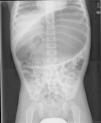

The second case involved a 3-year-old boy seen at the emergency room for daily episodes of abdominal pain the course is 2 months but vomiting, were only in the last days. The examination only revealed distension of the top half of the abdomen with marked tympanic sounds. Gastric volvulus was suspected and an abdominal radiograph done (Fig. 2) that confirmed it. A nasogastric tube was inserted and a fundal and anterior gastropexy performed. The patient had a favourable outcome.

The diagnosis is usually made by an abdominal radiograph and an upper gastrointestinal series,3 although the results of these studies may be normal.4 Thus, other imaging techniques, such as CAT, may be required if there is a high clinical suspicion and the previously mentioned studies are all normal. Depending on the axis of rotation, the volvulus is classified as organoaxial (54% of acute cases and 85% of chronic cases),1 mesenteroaxial (41% of acute and 10% of chronic cases),1 or combined.5 The findings may include gross gastric distension, abnormal position of the stomach, and two air-fluid levels in imaging studies with a “bird's beak appearance” at the esophagogastric junction, among others. In organoaxial volvulus, the stomach lies on a horizontal plane with the greater curvature superior to the lesser curvature. In mesenteroaxial volvulus, the gastroduodenal junction is superior to the oesophagogastric junction, and the stomach plane is vertical and has a spherical appearance.